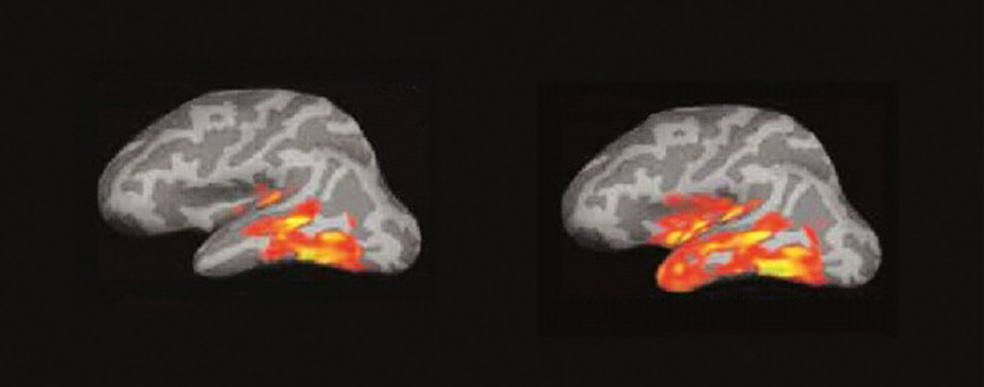

El cerebro del lector: un incendio de ideas

La imagen por resonancia magnética del cerebro de alguien que lee muestra algo parecido a un incendio forestal en un día de viento. Las pavesas vuelan y prenden nuevos conatos en diferentes zonas…

Entre 100 y 170 milisegundos. (A la izquierda) 1. Cuando leemos, cada palabra que ve nuestra retina produce un eco en la corteza cerebral. La primera señal eléctrica se aprecia en el polo occipital. (A la derecha) 2. La actividad se extiende a la región temporal izquierda, donde está el buzón del lenguaje, que aísla la forma visual de la palabra y la reconoce.